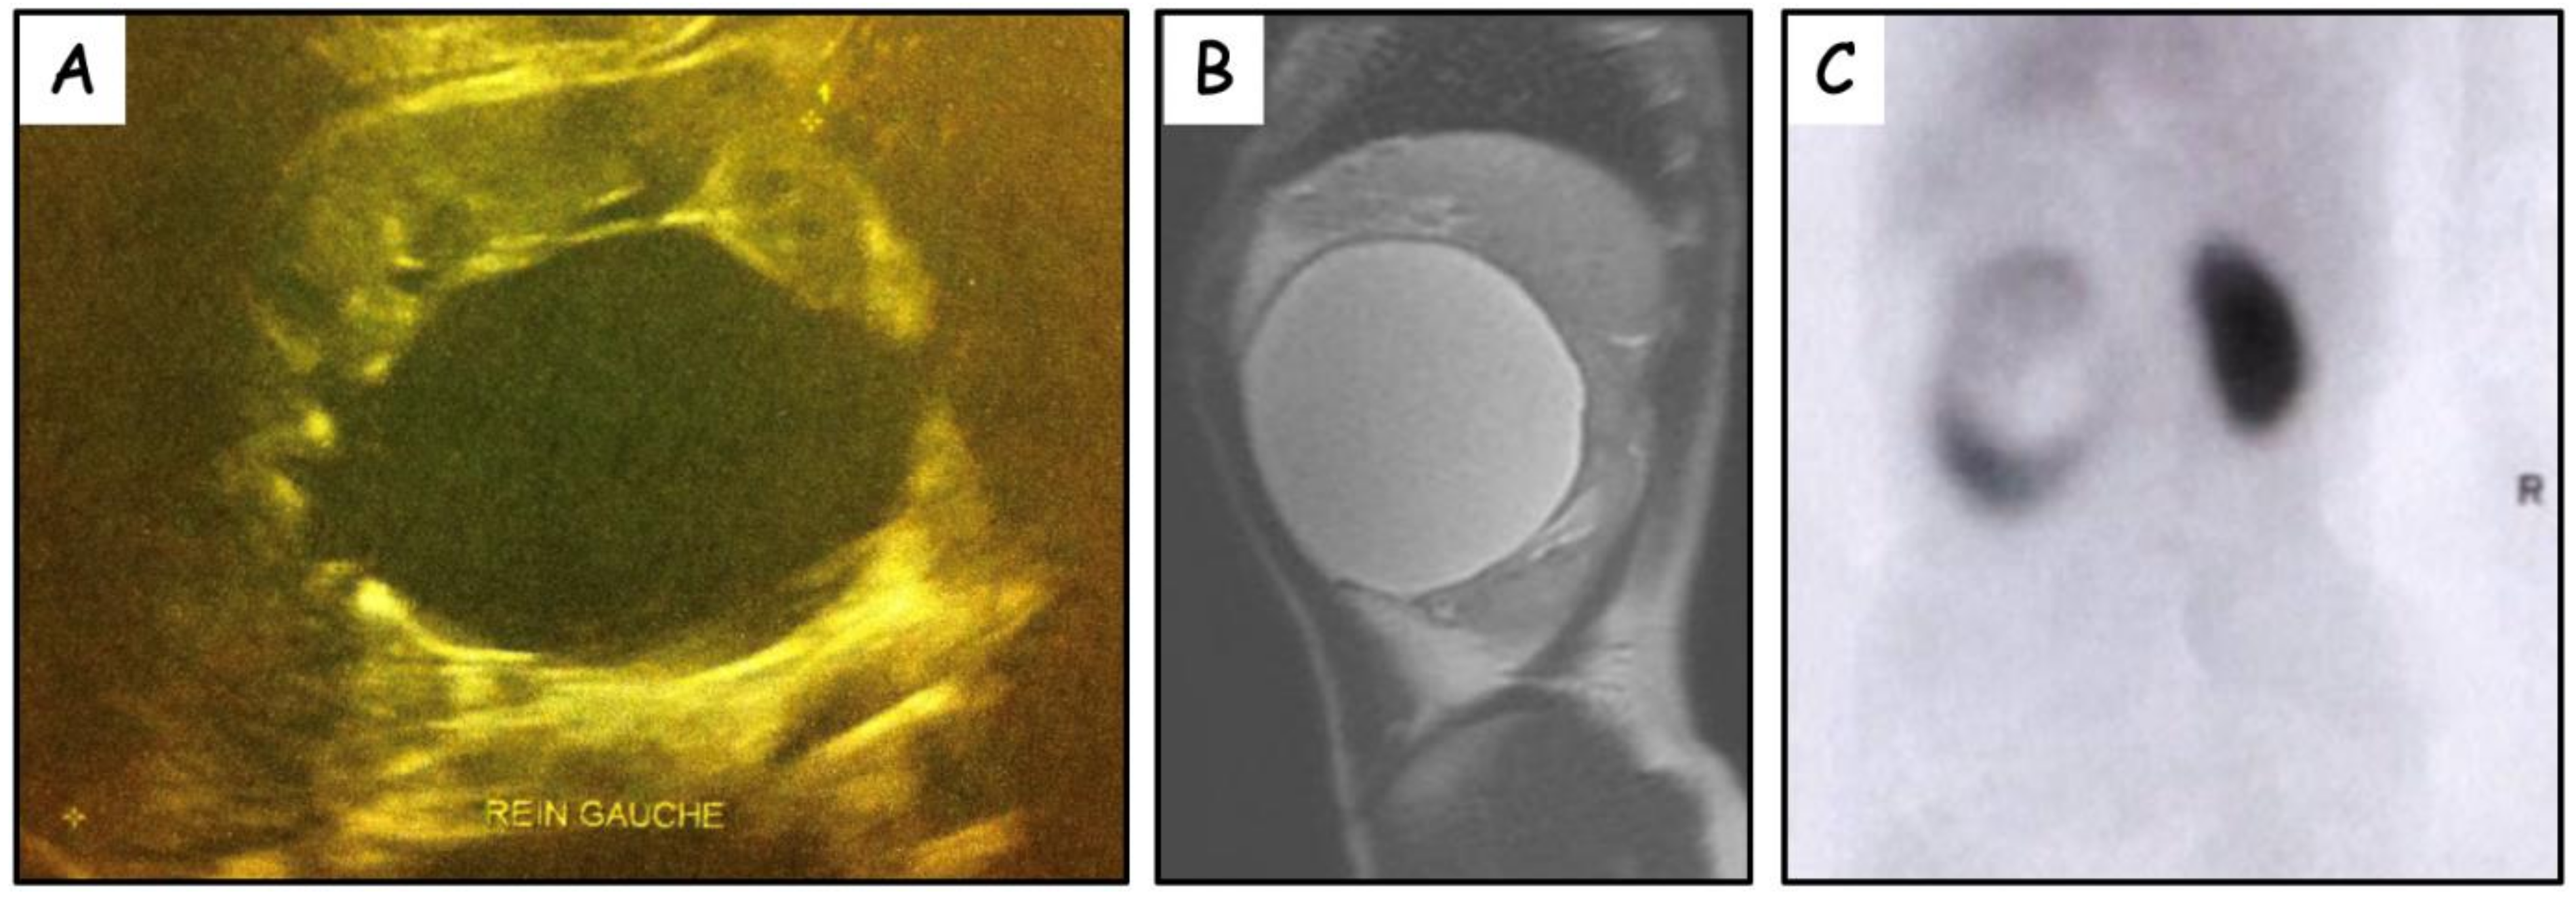

| Case # | Age | Presentation | Renal US | Size (mm) | MRI/CT Scan | Pre-op MAG3 RS | Approach | Preoperative Retrograde Pyelography | Intraoperative Retrograde Pyelography Methylene blue | Procedure | Follow-up (years) | Outcome | Post op MAG3 RS |

|---|---|---|---|---|---|---|---|---|---|---|---|---|---|

| 1-M | 18 months | Abdominal pain Vomiting | Pelvis dilatation | 42 | - | 48% | Subcostal flank incision | - | - | De-roofing | 7 | Asymptomatic | - |

| 2-F | 8 years | Abdominal pain | Pelvis dilatation | 85 | PPC | 38% | Laparoscopy | No pelvicalyceal dilatation | No communication | De-roofing | 4 | Asymptomatic | 51% |

| 3-M | 7 years | Renal colic Vomiting | Cystic mass | 55 | PPC | 21% | Subcostal flank incision | No renal pelvis | - | De-roofing | 5.5 | Asymptomatic | 17% |

| 4-F | 5 years | UTI Abdominal pain | Cystic mass | 60 | PPC | - | Laparoscopy | No renal pelvis | - | De-roofing | 3.5 | Asymptomatic | - |